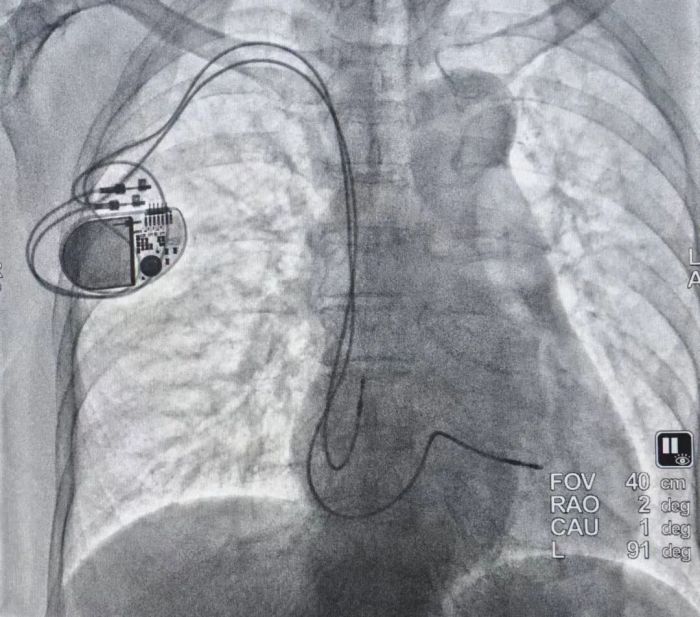

一段跨越二十年的医患信任,近日在中南大学湘雅二医院桂林医院迎来了温暖的续章。面对一位因早年手术失败而心怀阴影的八旬老人,心血管内科团队以一台高难度的右侧锁骨下双腔起搏器植入术,用精湛的医术回应了患者一家以生命相托的信任,解决了困扰患者多年的“心头之患”。

时光回溯至二十年前,患者曾因心脏问题在外院接受了起搏器植入手术。然而,术后因电极导线断裂伴发感染,整套起搏系统不得不被全部移除。这次曲折的治疗经历,在患者心中投下了长长的阴影,致使在此后近二十载岁月里,他对“再次植入起搏器”这个选项,始终心怀抗拒、不愿触及。

面对这份沉甸甸的信任与高难度的手术挑战,由刘启明教授团队的核心成员陈明鲜副主任主刀,为患者实施了右侧锁骨下双腔起搏器植入术。整台手术顺利圆满,术后起搏参数测试理想。这一成功,不仅标志着患者重获健康心跳,更一举驱散了萦绕在他心头长达二十年的阴霾。